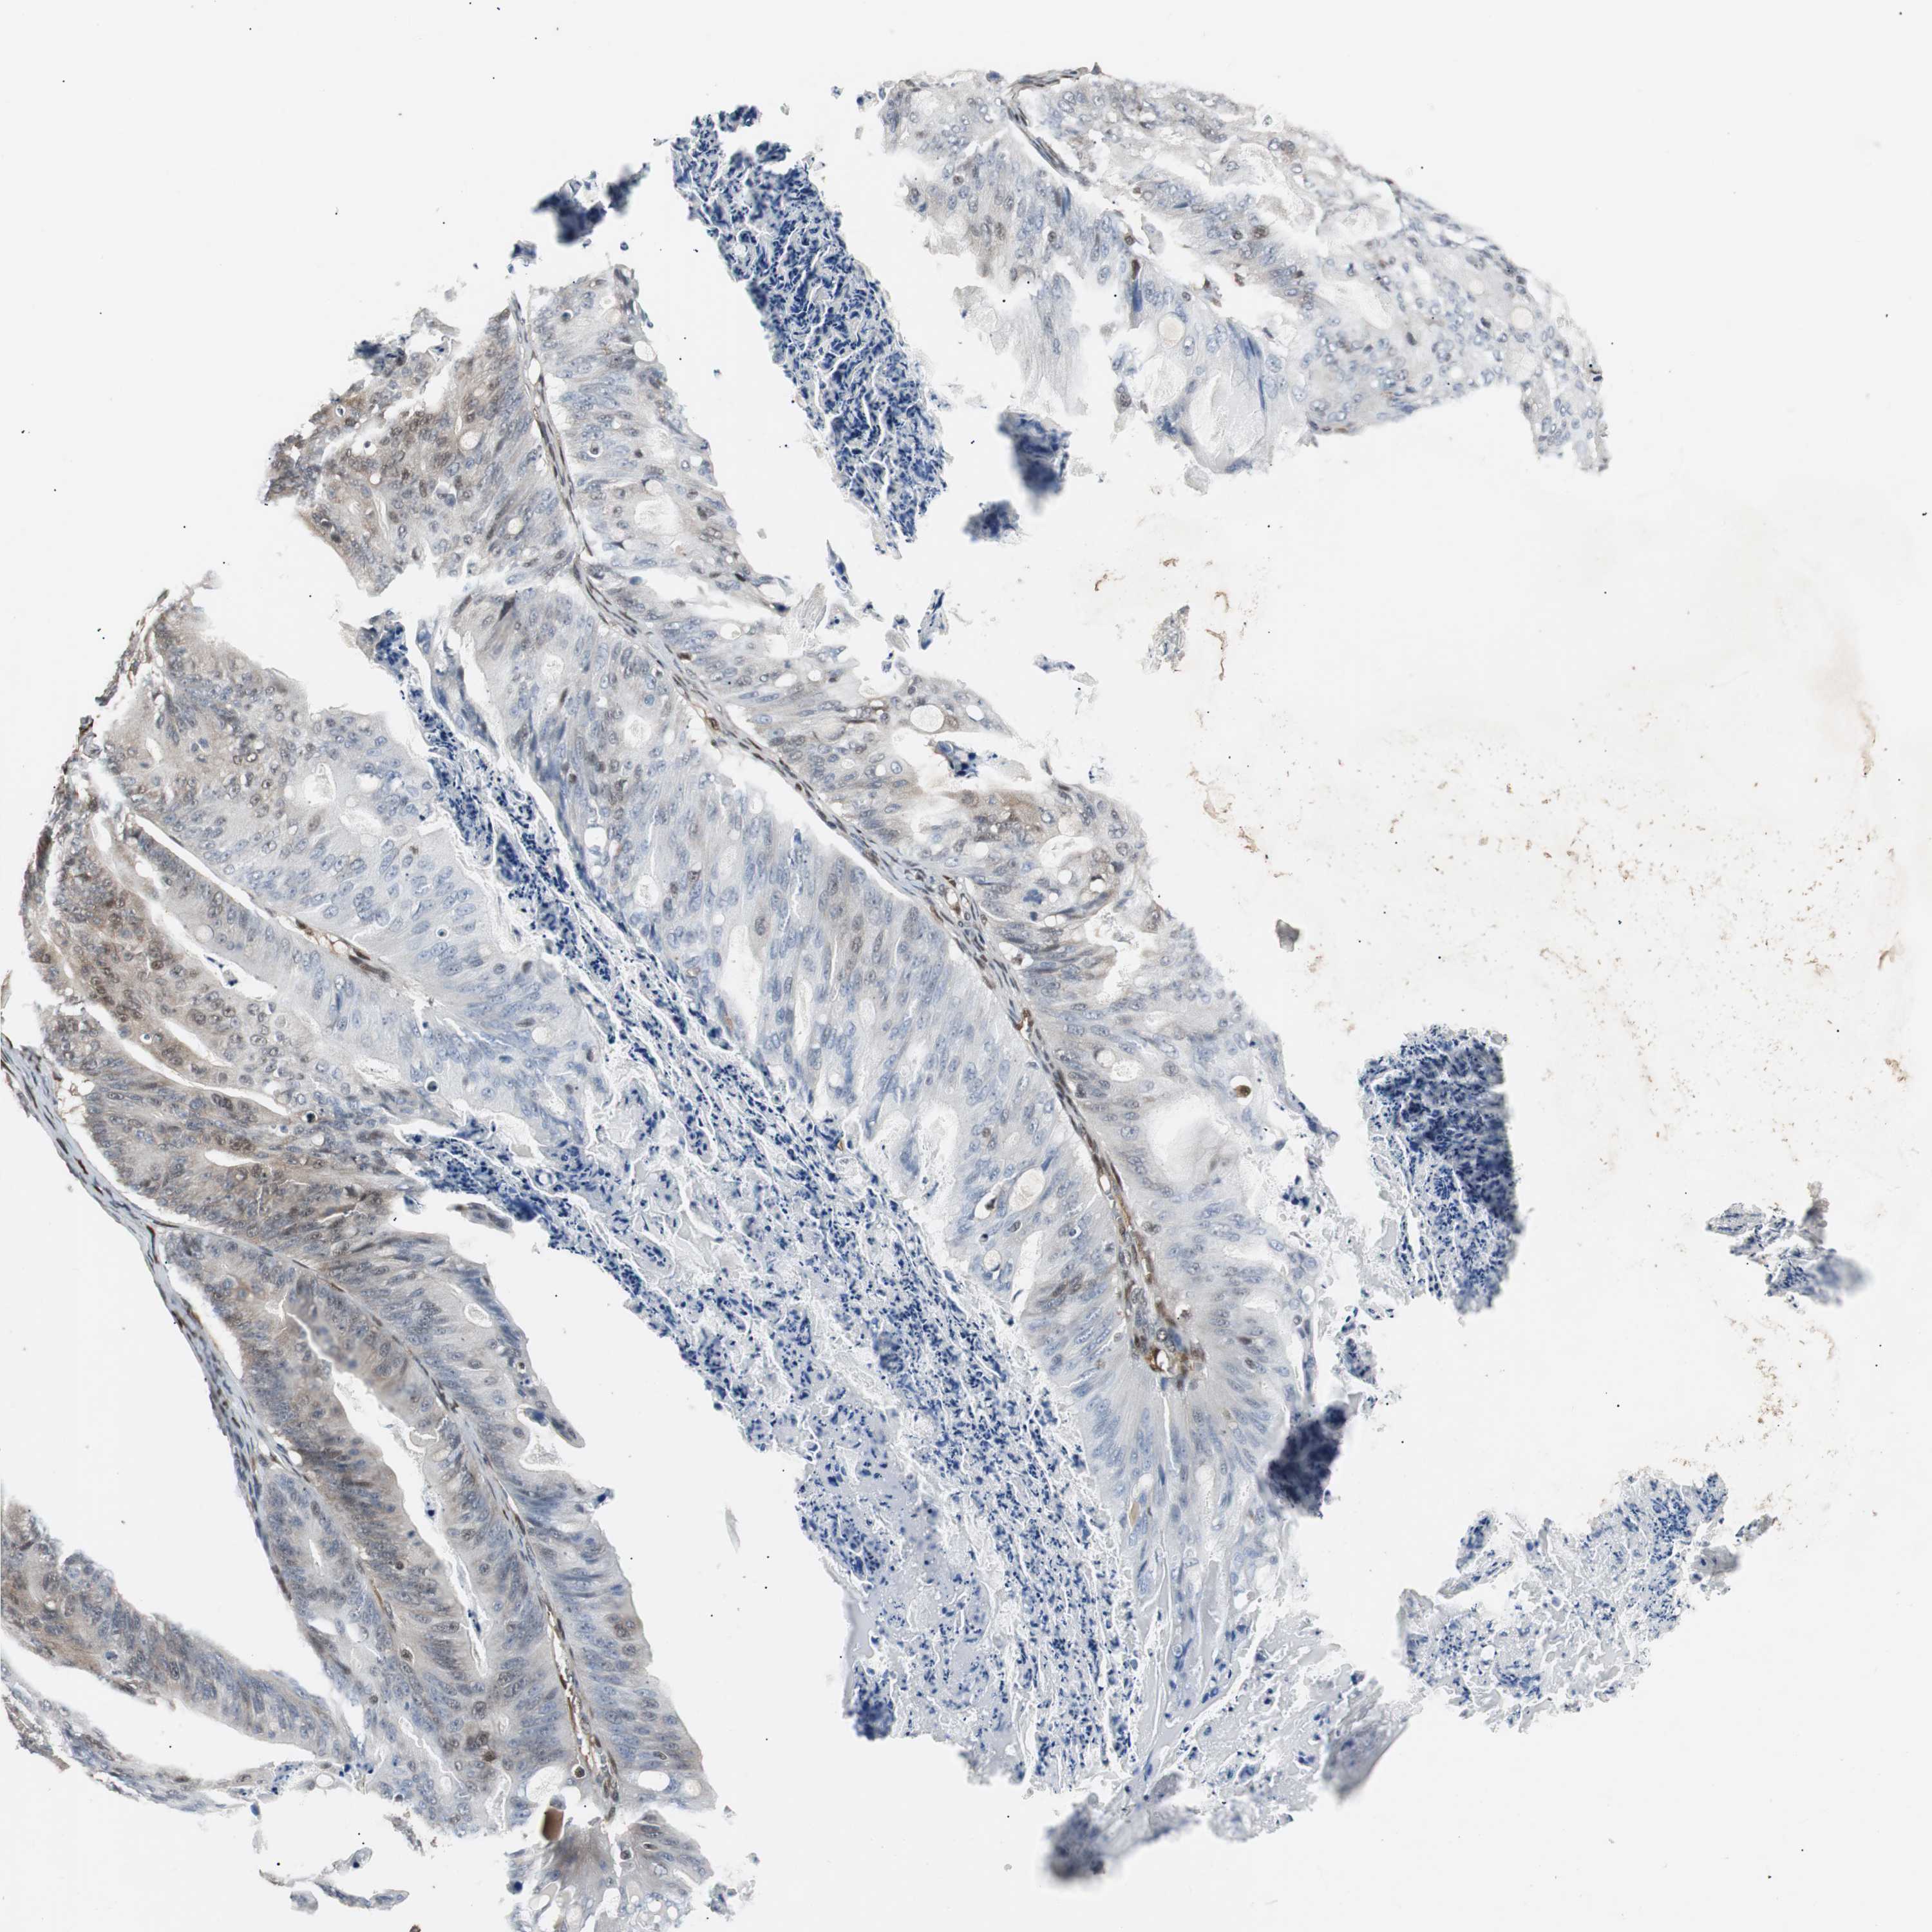

OVARIAN CANCER - Protein expressioni

A mouse-over function shows sample information and annotation data. Click on an image to view it in a full screen mode. Samples can be filtered based on level of antibody staining by selecting one or several of the following categories: high, medium, low and not detected. The assay and annotation is described here.

Note that samples used for immunohistochemistry by the Human Protein Atlas do not correspond to samples in the TCGA dataset.

Antibody stainingi

Antibody staining in the annotated cell types in the current human tissue is reported as not detected, low, medium, or high, based on conventional immunohistochemistry profiling in selected tissues. This score is based on the combination of the staining intensity and fraction of stained cells.

Each image is clickable and will lead to virtual microscopy that enables deeper exploration of all samples and also displays staining intensity scores, fraction scores and subcellular localization as well as patient and tissue information for each sample.

HPA022953

Carcinoma, endometroid

Cystadenocarcinoma, mucinous, NOS